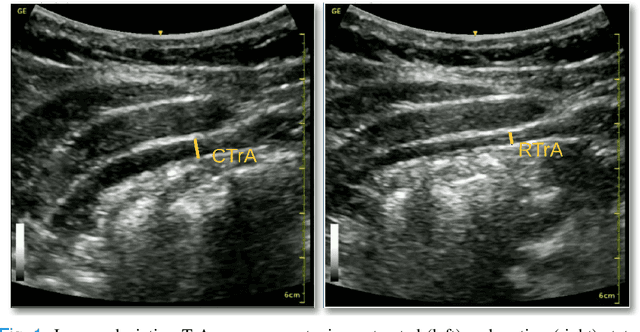

Abstract:Health professionals extensively use Two- Dimensional (2D) Ultrasound (US) videos and images to visualize and measure internal organs for various purposes including evaluation of muscle architectural changes. US images can be used to measure abdominal muscles dimensions for the diagnosis and creation of customized treatment plans for patients with Low Back Pain (LBP), however, they are difficult to interpret. Due to high variability, skilled professionals with specialized training are required to take measurements to avoid low intra-observer reliability. This variability stems from the challenging nature of accurately finding the correct spatial location of measurement endpoints in abdominal US images. In this paper, we use a Deep Learning (DL) approach to automate the measurement of the abdominal muscle thickness in 2D US images. By treating the problem as a localization task, we develop a modified Fully Convolutional Network (FCN) architecture to generate blobs of coordinate locations of measurement endpoints, similar to what a human operator does. We demonstrate that using the TrA400 US image dataset, our network achieves a Mean Absolute Error (MAE) of 0.3125 on the test set, which almost matches the performance of skilled ultrasound technicians. Our approach can facilitate next steps for automating the process of measurements in 2D US images, while reducing inter-observer as well as intra-observer variability for more effective clinical outcomes.